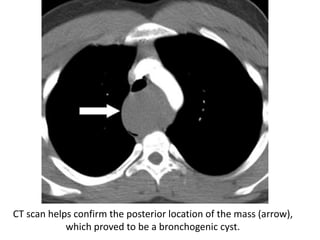

Posteroanterior chest radiograph demonstrates a subcarinal abnormality with

increased opacity (*), splaying of the carina, and abnormal convexity of the

upper and middle thirds of the azygoesophageal line (arrowheads)

Corresponding CT scan helps confirm a subcarinal mass (arrow),

which proved to be a bronchogenic cyst.